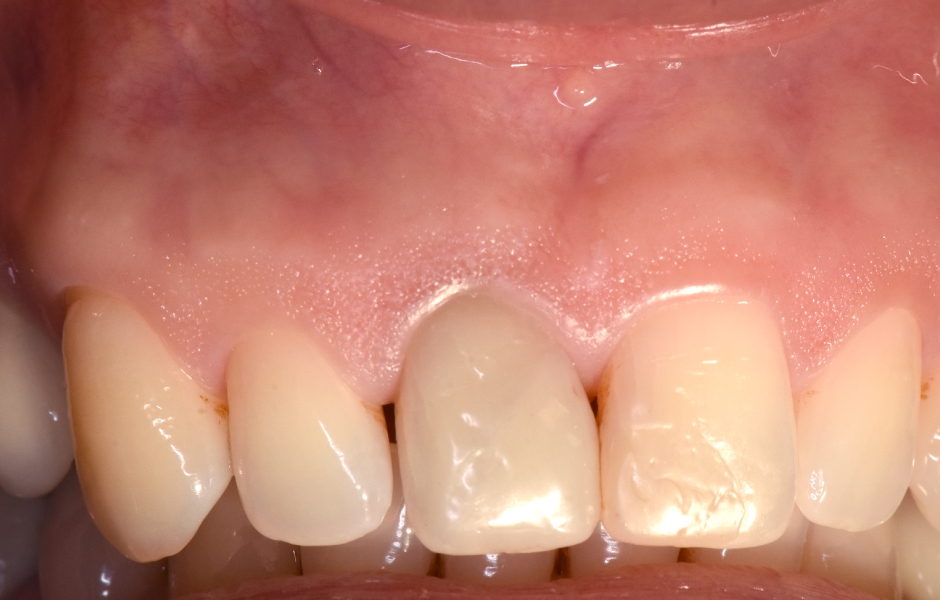

Obr. 1.5: Odstranění sutur po 48 hodinách a kontrola po třech letech – kompletní absence jizvy.

Obr. 1.6: Kontrola po třech letech.

Po pořízení pooperačního rentgenového snímku je operatér připraven uvolnit a reponovat lalok a provést suturu, opět za použití operačního mikroskopu. Lalok se vrací do své původní polohy, hojení probíhá per primam intentionem a konečným výsledkem je chirurgický zákrok bez tvorby jizevnaté tkáně.

Stehy se odstraňují po 24–48 hodinách a poté je pacient pozván na recall každých 6 měsíců po dobu dvou let, aby bylo možné hodnotit a dokumentovat kvalitu hojení, které se vyskytuje ve velmi vysokém procentu případů – téměř 100 %.